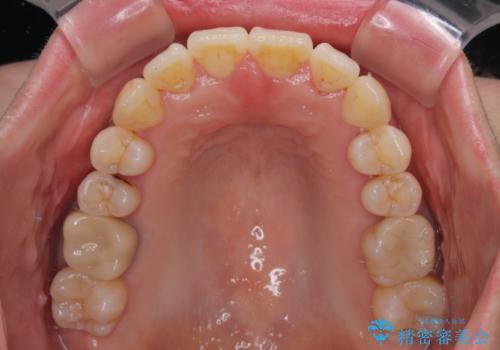

- 上下前歯のデコボコを気にして来院された患者様です。

デコボコは顕著であるものの、口元の突出感は強くないため、非抜歯にて矯正治療を行うこととしました。

装置はワイヤー装置でもマウスピースでも対応可能でしたが、より目立たない装置をご希望とのことで、インビザラインにて矯正治療を行うこととしました。

元々の叢生と歯肉退縮傾向になる歯肉であったため、ブラックトライアングルが目立つことが想定されました。

治療過程でブラックトライアングル改善のため、IPR(歯と歯の間を削る)を活用しました。